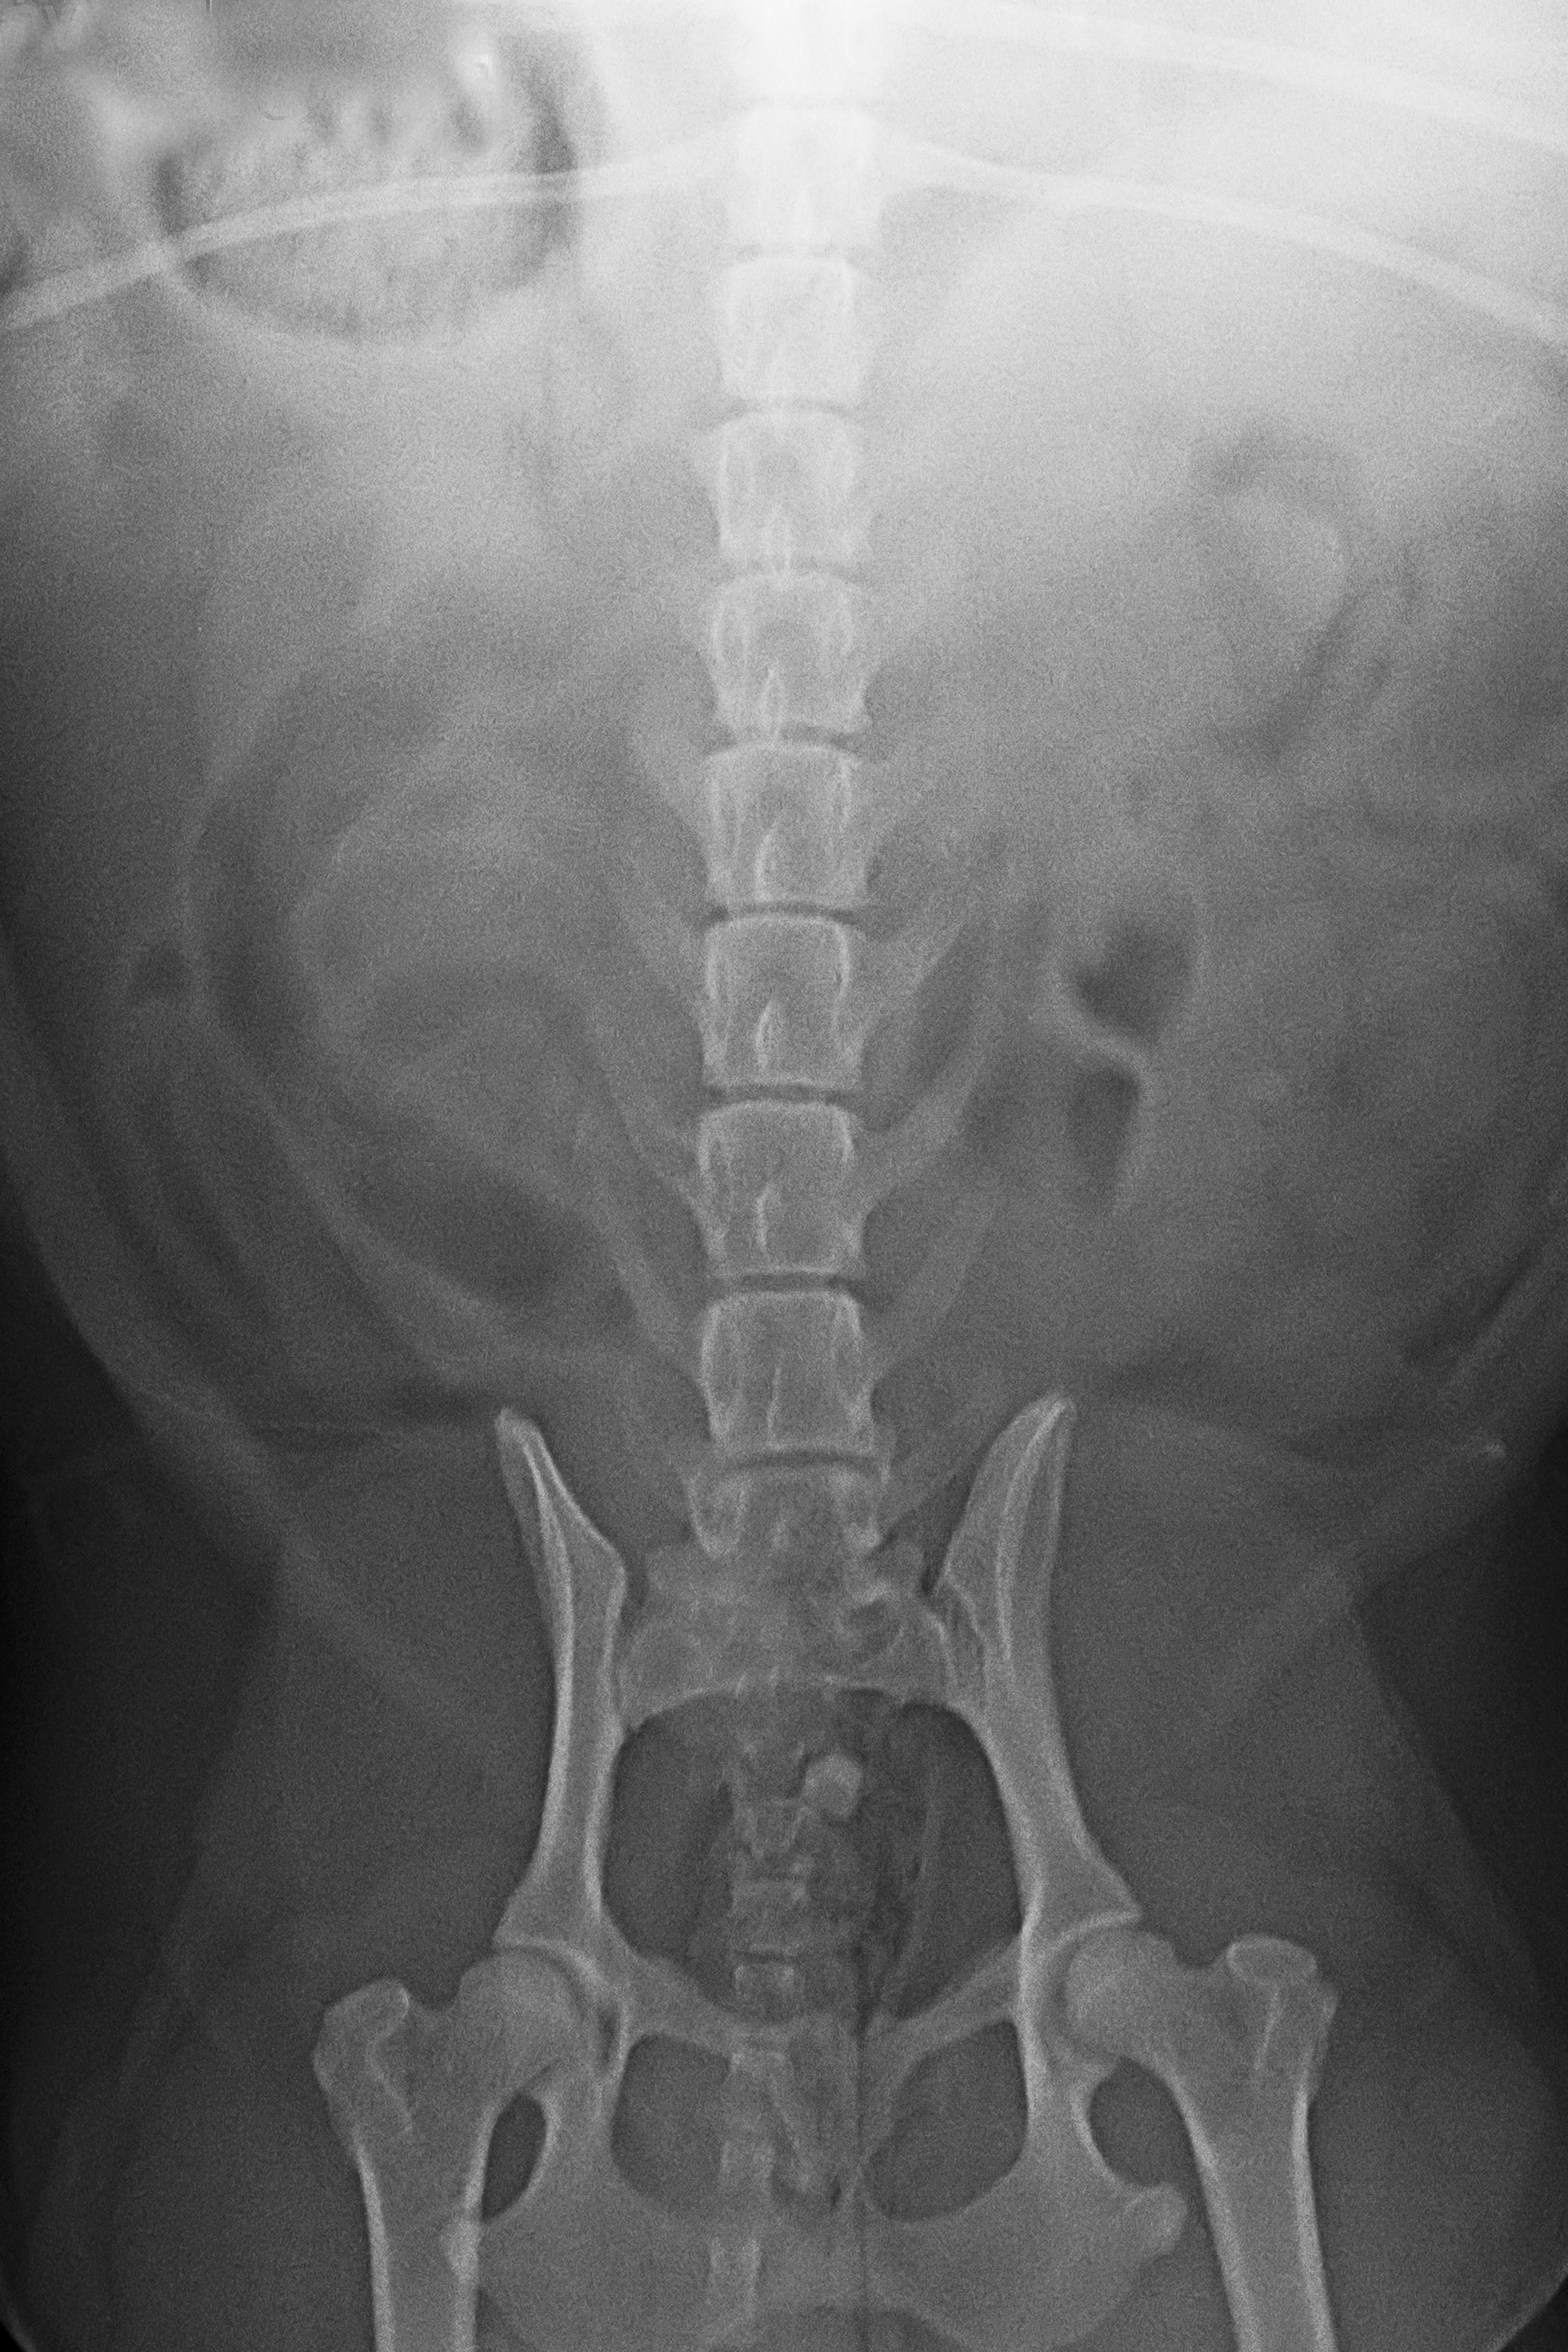

(3) 7 měsíců VD 1

(3) typ 3 po korekci polohy pánve

(5) typ 3 páteř VD